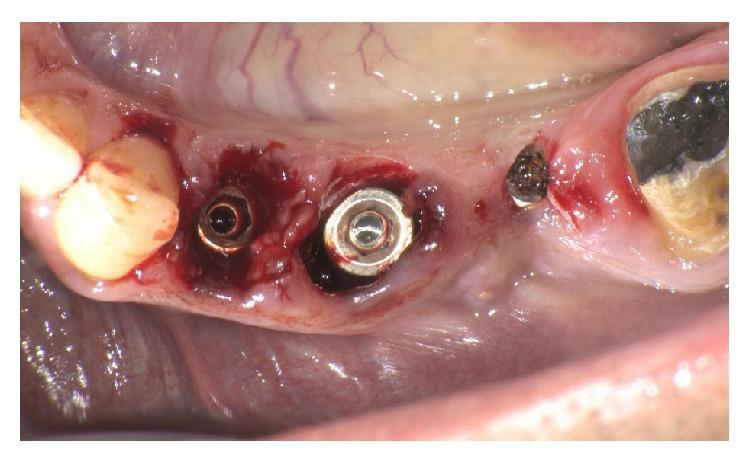

The extraction of teeth results in rapid bone resorption both vertically and horizontally in the first month. The loss of alveolar ridge reduces the chance of implant rehabilitation. Atraumatic extraction, implant placement in extraction socket, and an immediate prosthesis have been proposed as alternative therapies to maintain the volume and contours tissue and reduce time and cost of treatment. The immediate load of implants is a universally practiced procedure; nevertheless a successful procedure requires expertise in both the clinical and the reconstructive stages using a solid implant system. Excellent primary stability and high bone-implant contact are only minimal requirements for any type of implant procedure. In this paper we present a case report using a new type of implants. The new type of implants, due to its sophisticated control system of production, provides to the implantologist a safe and reliable implant, with a macromorphology designed to ensure a close contact with the surrounding bone.